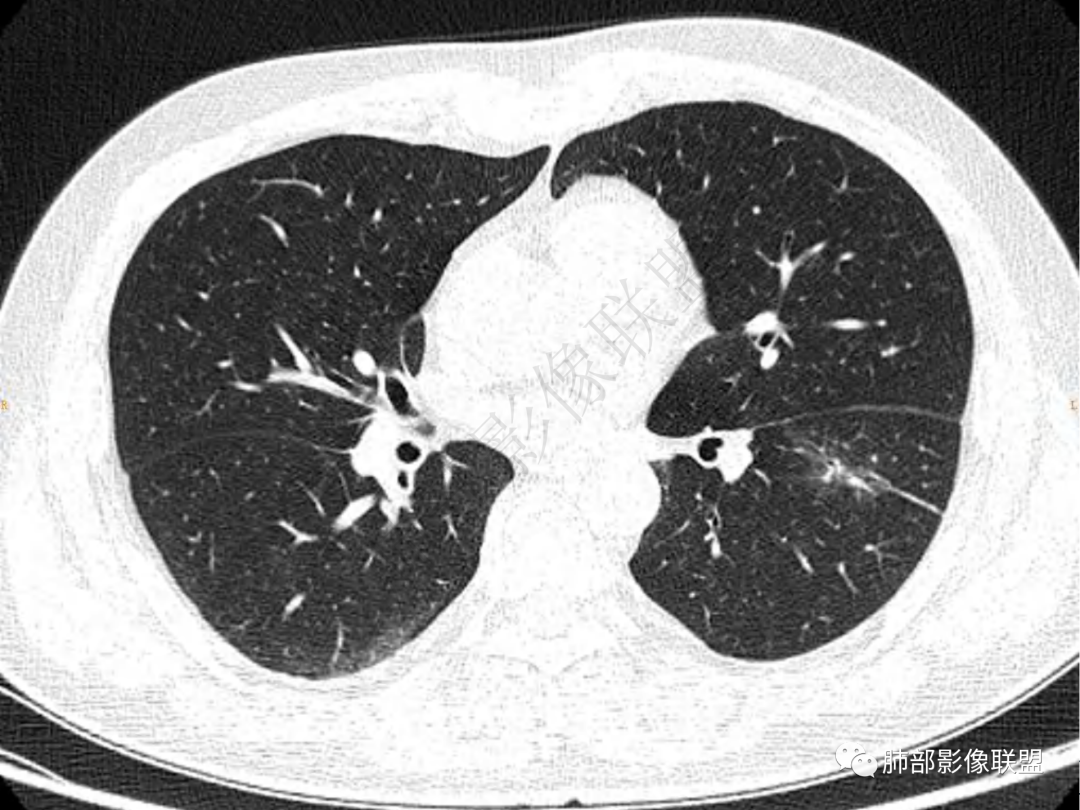

2.左肺下叶团片影,跨背段及内前基底段,实性部分类椭圆形,密度不甚均匀,可见毛刺及棘状突起,未见典型分叶及胸膜凹陷。病灶上下缘可见相应肺段支气管旁进侧出,管壁轻度增厚,未见狭窄阻塞。

3.周边较大范围磨玻璃影,边界相当模糊,小叶增厚明显。注意叶裂另一侧、左肺舌段亦可见磨玻璃影及增厚的小叶间隔。未见明确卫星病灶。

4.实性部分不均匀环形强化并显示一小范围低密度坏死区或空洞。较之肺窗,整体纵隔窗范围较小,提示病灶并不十分密实。抑或为不同时段图像。

肺脓肿:可宽基底与胸膜相连,附近胸膜增厚——炎性特点

肺脓肿:边界模糊不清,或者块影为类圆形,无明显分叶,边缘平直为主,刀切征——炎性特点三、病灶周围特点:肺脓肿:病灶非远端有片状GGO——炎性特点四、近端支气管阻塞:肺脓肿:常有引流支气管伴管壁增厚或者支气管沿洞壁走行。五:坏死壁:肺脓肿:大多壁厚,少数壁薄,没有壁结节,内壁清楚光整——炎性特点